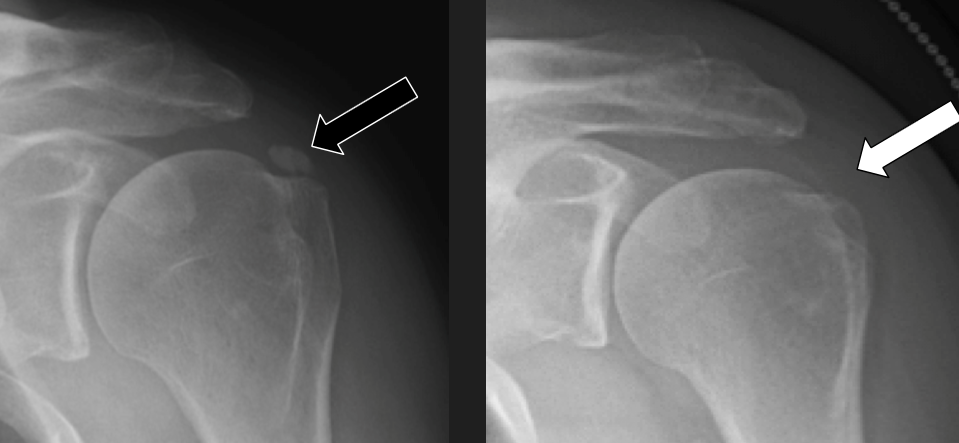

Poleg kliničnega pregleda je potrebna RTG diagnostika in UZ preiskava ramena, v določenih primerih tudi preiskava z magnetno resonanco. Običajno se vnetje zdravi s počitkom, analgetično terapijo, fizikalno terapijo. V določenih primerih svetujemo tudi terapijo z udarnimi valovi (ESWT).

V kolikor so kalcinati večji od 8mm in so enakomerne strukture lahko pod ultrazvočno kontrolo opravimo tudi punkcijo kalcinata in kalcinat izperemo. Poseg se opravi v lokalni anesteziji in traja približno 30 minut. Bolečina lahko traja tudi nekaj dni po posegu. V teh primerih svetujemo jemanje analgetikov. Nekaj dni po posegu priporočamo postopno stopnjevanje aktivnosti, izvajanje vaj, plavanja, nordijske hoje in fizikalne terapije in po 2 -3 mesecih vrnitev željenim aktivnostim.